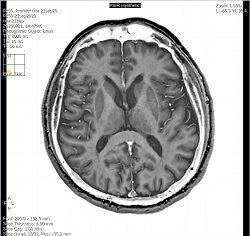

- By default, a 6-viewport display is launched with 6 unique MAGiC images.

Table 1. Right-click menu to change image contrast in the active viewport Right-click selection Right-click selection Click T1W to change the image contrast to synthetic T1-weighted.

Click T2W to change the image contrast to synthetic T2-weighted.

Click PDW to change the image contrast to PD-weighted synthetic.